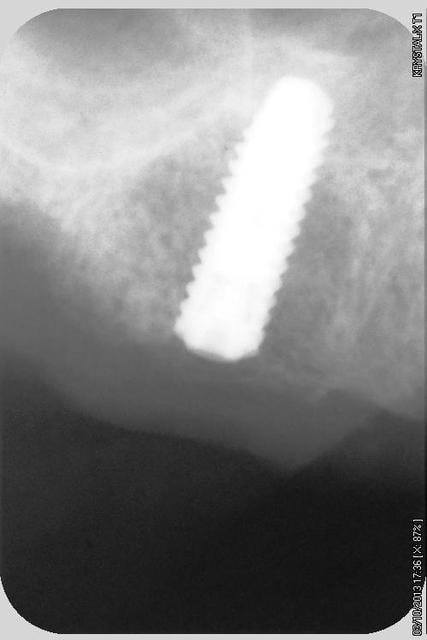

quelques radios.

oui, bien sur ce sont des Tatum D1 en bas et D4 en haut